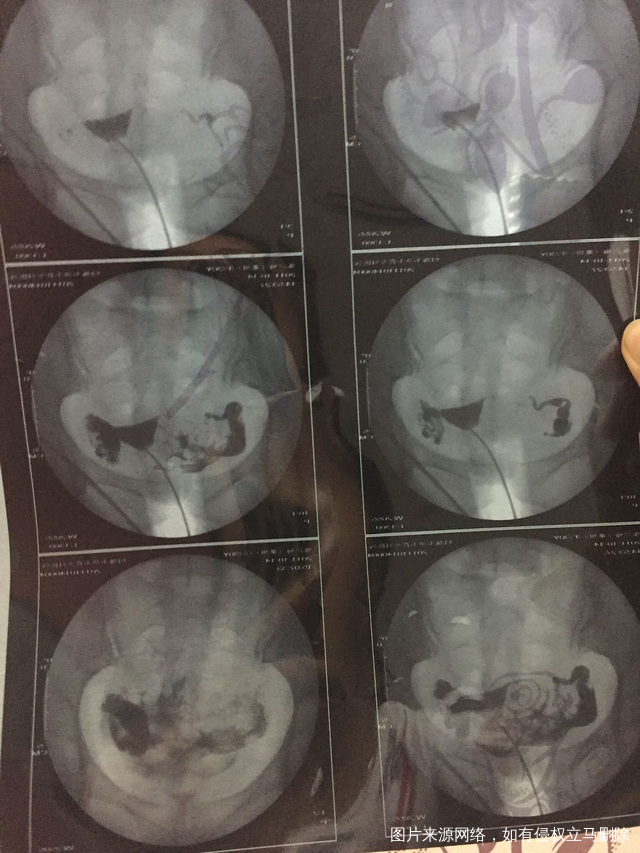

这种必须做手术么还是取了胚胎不是非要做

这个手术不是非得要马上做,需要根据你的年龄、生育计划等来综合评估并权衡利弊后再决定是否需要手术以及什么时候做。如果是做试管通常为了避免输卵管积液及炎症因子逆流至宫腔影响胚胎着床等,会行输卵管结扎等手术,这个手术通常在移植前完成